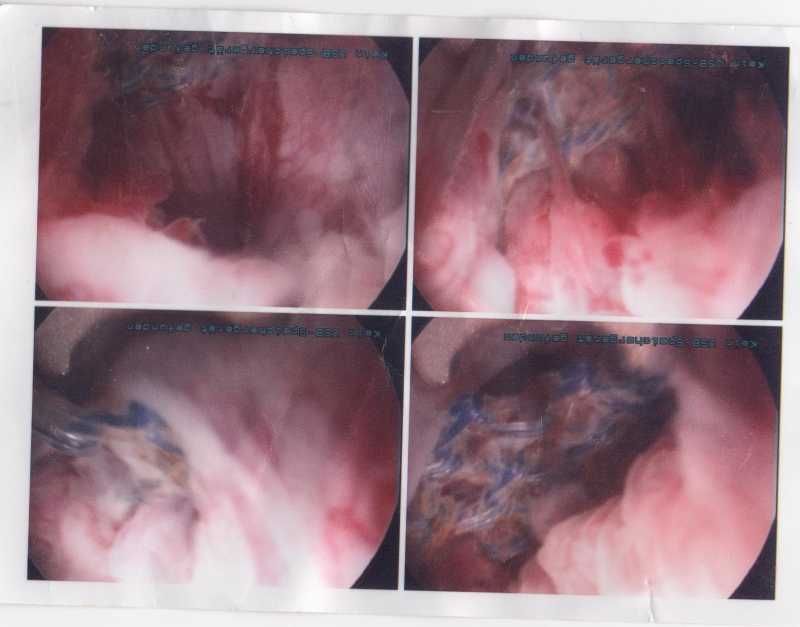

Das blaue ist das TVT Band

Au weia - das sieht gar nicht gut aus, liebe Moni!